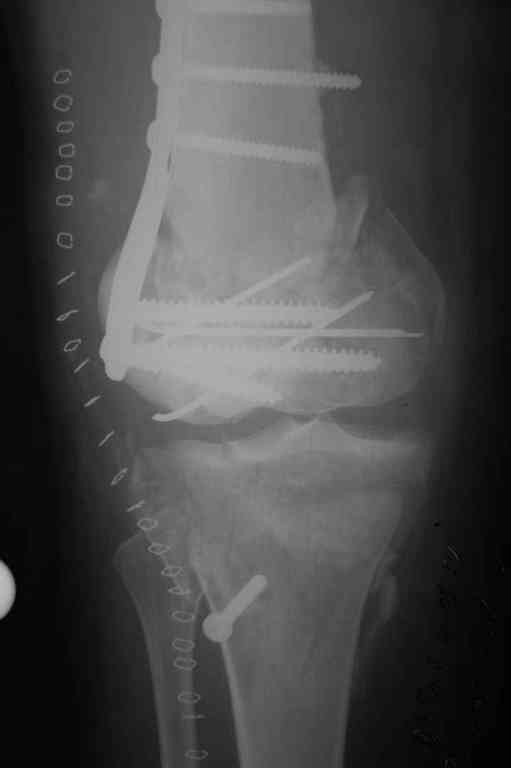

Тамошние доктора выполнили ПХО с удалением фрагментов латерального мыщелка бедра. Наложен АВФ. По возвращению в Украину через 1,5 месяца АВФ демонтирован. И так как смещение фрагментов бедра не устранено, было принято решение после заживление ран от стержней выполнить МОС. Не сколько для четкой анатомической репозиции сколько для подготовки к установке эндопротеза в будущем. Что и было выполнено 10 августа. Интраоперационная картина следующая. Дефицит практически всего латерального мыщелка бедра. Была выполнена попытка закрепить то что осталось от мыщелка, но он развалился на фрагменты. ВЫполнен ситуационный синтез спицами. Дефект заполнили бикортикальным трансплантатом из крыла подвздошной кости, МОС страйкеровским фиксатором. В послеоперационном периоде к 10 дню начались боли, гипертермия. Повышение СОЭ, лейкоцитоз. Посев крови транзиторная бактериемия золотистого стаф. Взяли в операционную. Выполнили дренирование сустава и области п\о раны. Получили гематому фактически с гноем. Температура нормализовалась. Назначили ванкомицин по 1000 мг 2 раза в день.который принимает с 28 августа по сей день. Температура нормальная, СОЭ на убыль. Посевы отделяемого стафилококк 2 ст активности. Но отделяемое по дренажам продолжает идти в достаточном количестве. Взял посев, сеется стаф. 3 ст активноси. К ванкомицину, понятно, слабочувствителен. Что в этой ситуации посоветуете?

Коллеги фиксатор Numelock II

На вашем снимке из-за ротации трудно угадать положение пластины, и желательно сделать снимок с захватом верхнего участка бедра.

Одинокий кортикальный шуруп не удержит тибиальный бугор, сустав тибиал плато оставлен без репозиции и фиксации.

План с протезированием чересчур агрессивный, больная слишком молодая. В данный момент для удержания конструкции необходимо установить наружный фиксатор между бедром и голенью. Обработку продолжать с применением антибиотиков и вакуумирования.

Здесь применение материала Plexur http://www.plexur.com для пластики при дефектах кости у больной с огнестрельной раной латерального тибиал плато с повреждением малоберцового нерва. Несмотря на интактный медиальный мышелок, для профилактики от вальгуса установлен АВФ и сделана ангиограмма.

После нескольких обработок и вакуумирования, поэтапно сделана фиксация тибиального бугра шурупами. И окончательную фиксацию закончили латеральной пластиной для тибиал плато и установкой пластического материала.